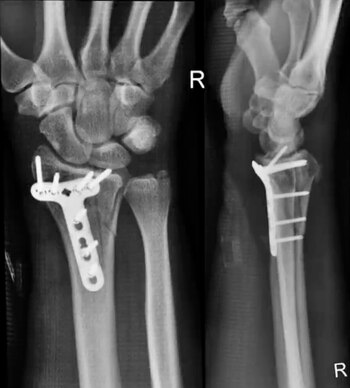

"Con el impacto de la caída (a casi 80 kilómetros por hora), mi muñeca derecha sufrió una fractura distal fragmentada del radio, que requirió cirugía", escribe en sus comentarios al final del video en Youtube. "Me instalaron una placa de titanio y siete tornillos, y me dieron de alta la tarde siguiente".